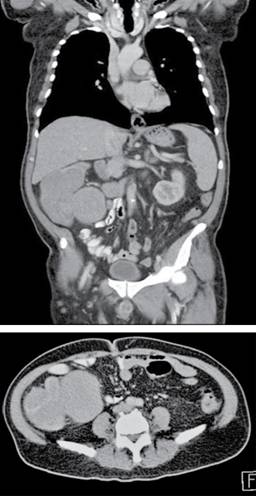

Paciente masculino de 62 años de edad sin antecedentes médicos, referido al Servicio de Cirugía General por presentar tres meses de evolución con sangrado de tubo digestivo bajo caracterizado por evacuaciones melénicas, astenia, adinamia, dolor abdominal localizado sobre todo en la fosa iliaca derecha y pérdida de peso de aproximadamente 10 kg en los últimos dos meses. Dentro de sus exámenes de laboratorio sólo se reportó anemia (hemoglobina: 10.1) como única alteración. Se realizó una tomografía abdominopélvica con contraste intravenoso (Figura 1), la cual reportó una imagen hipodensa de 12 × 12 cm en el ciego y colon ascendente, compatible con neoplasia de colon; no se describieron adenopatías ni evidencia de lesiones metastásicas. Se llevó a cabo una colonoscopia (Figura 2), que mostró pared engrosada en el ciego y colon ascendente, con múltiples lesiones polipoides de 1 a 2 cm de diámetro que se extendían hasta el ángulo hepático, engrosamiento difuso a nivel del colon ascendente con estenosis del 50% de la luz; el reporte final fue síndrome polipósico con neoplasia de colon asociada. Se tomaron múltiples biopsias del tumor y pólipos de mayor tamaño. El reporte histopatológico definitivo concluyó linfoma de colon variedad de células B (CD 20 positivo) y con componente de poliposis linfomatosa múltiple (Figura 3). El paciente fue programado para cirugía. Se efectuó de forma convencional hemicolectomía derecha extendida con íleo-transverso anastomosis laterolateral con grapadora lineal. La evolución fue satisfactoria; el paciente egresó al sexto día postoperatorio. Se le dio seguimiento por la consulta de oncología.

Figura 1: Tomografía abdominopélvica con contraste intravenoso, imagen hipodensa de 12 × 12 cm en el ciego y colon ascendente.